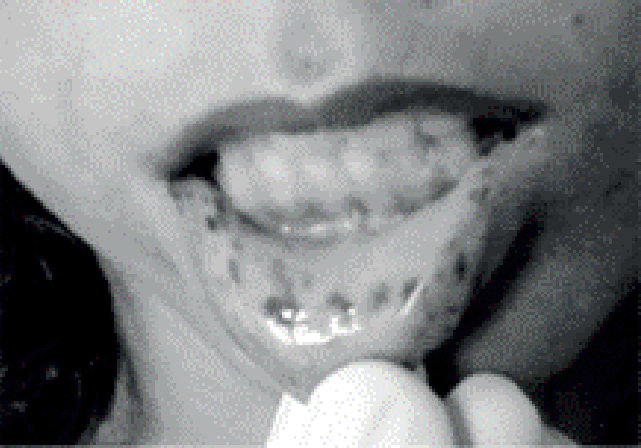

- Sinal Patognomônico: Melanose (manchas café-com-leite) em lábios e mucosa oral.